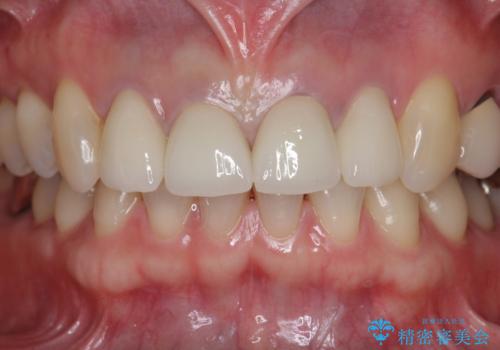

- 44万円(仮歯・ジルコニアクラウン×4)費用は治療当時の料金となります

金属を用いないジルコニアセラミッククラウンは透明感の再現性に優れ、審美性と自然な仕上がりの両立を期待することができます。